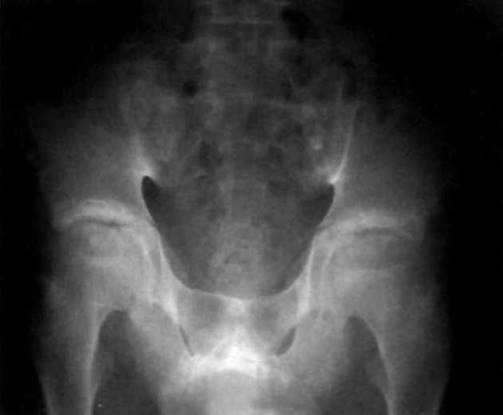

Рис. 23-21. Рентгенограмма таза больного ЮАС: сакроилеит IV стадии - полный анкилоз крестцово- подвздошных сочленений и анкилоз симфиза.